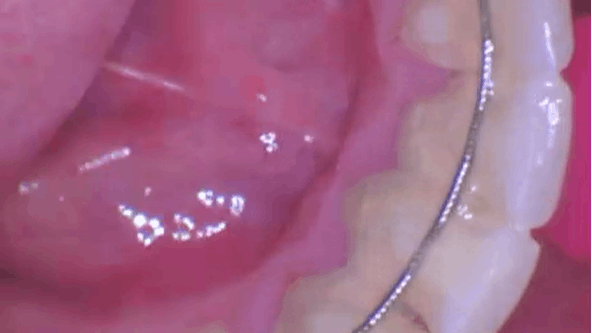

photo of a retainer on the bottom teeth

Amber Auger, MPH, RDH, presents a case study on scaling and root planing with glycine-based air polishing.

June 9, 2025